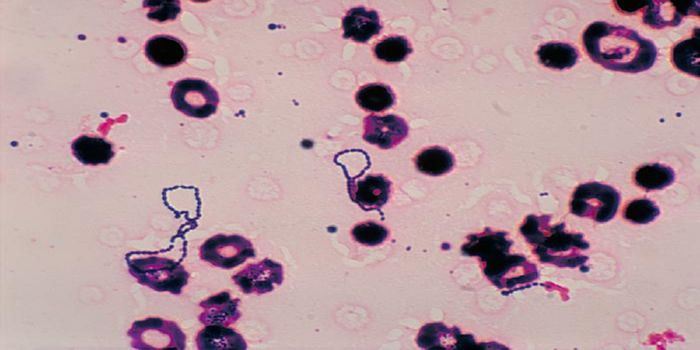

MAR 17, 2017Health & MedicineThe first human case of babesiosis was reported in 1957; until then it was thought of as a disease plaguing domes ...